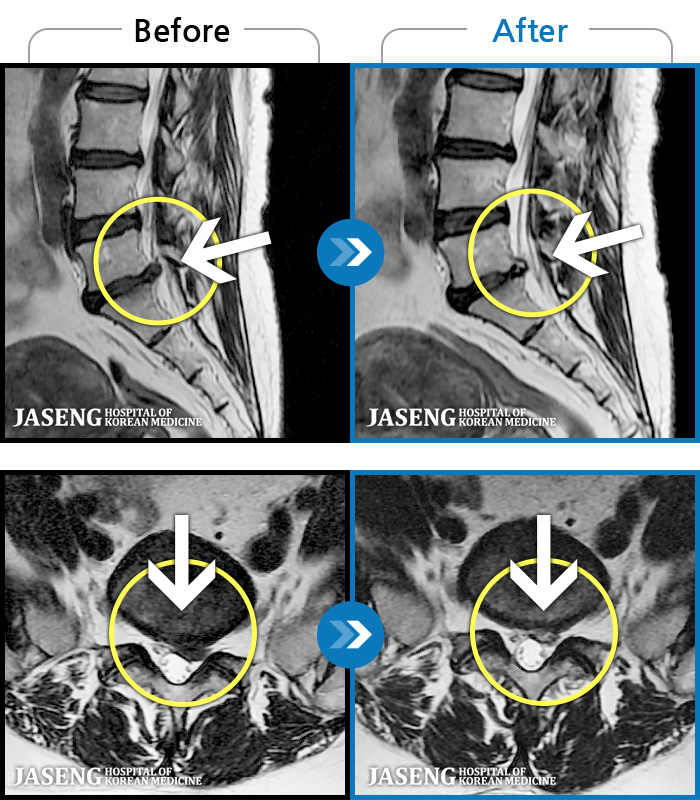

1,245 MRI ũ ʸ Ȯϼ.